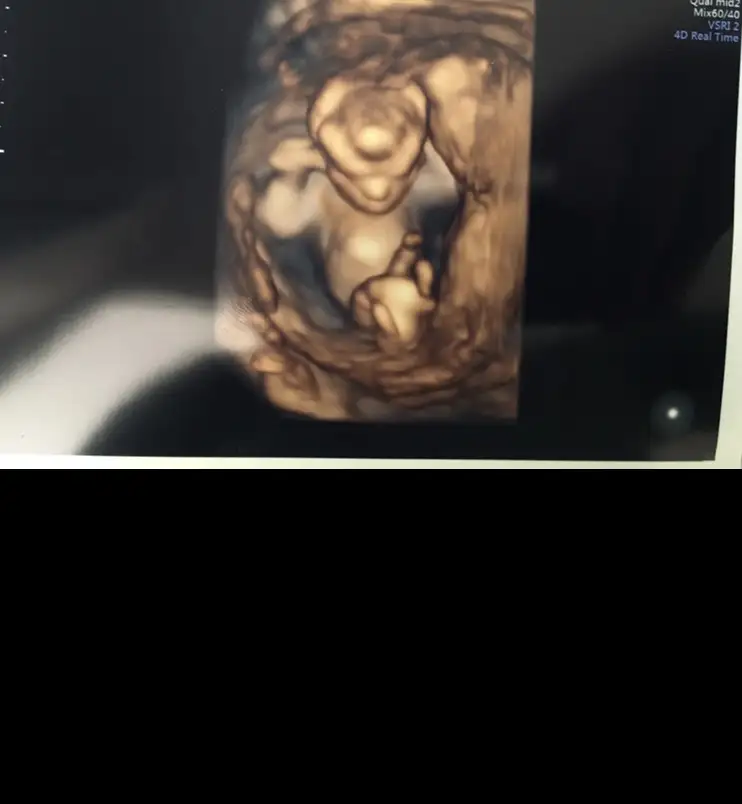

Videodan bir tane daha aldım görüntü. Ama böyle olmayacak sanırım. 🤔 çok merak ediyorum cinsiyeti

Eklentiler

• 72E4E40A-09F6-4A96-B283-259E526F5F80.webp

72E4E40A-09F6-4A96-B283-259E526F5F80.webp

16,3 KB · Görüntüleme: 65